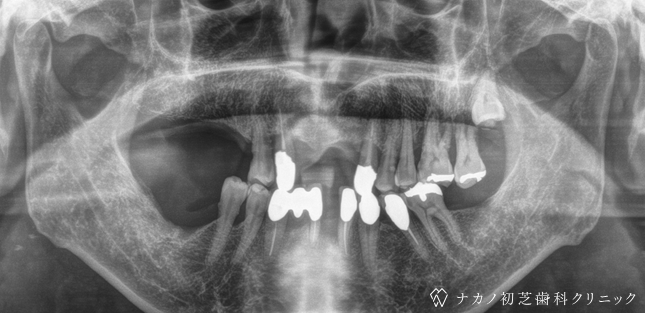

インプラント・13本 (60代女性)

BEFORE

年齢 60代女性

治療内容 インプラント治療13本(骨造成の併用)

インプラント治療とは、歯を抜いた所にチタン製の人工歯根を埋入し、その上に歯を入れる方法です。骨を増やすことで、より審美的に治療が出来ました。費用 1本 400,000円(税込 440,000円)

リスク・副作用

腫れ・疼痛・違和感を感じるなどの症状を生じることがあります。